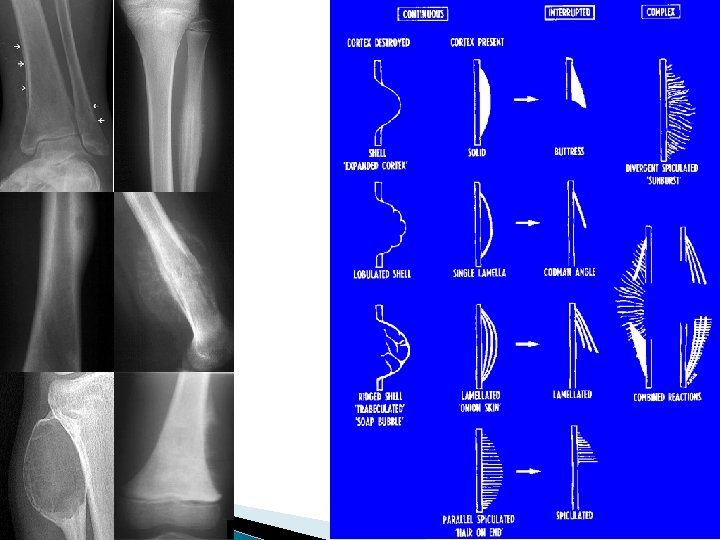

Periosteal Reaction � Periosteal reaction must mineralize to be seen on X ray ( 10 days – 3 weeks) � Configuration of periosteal reaction ◦ ◦ Nature of inciting process Intensity Aggressiveness Duration

Periosteal Reaction � Thick, uninterrupted ◦ long standing process, often non-aggressive �stress fracture �chronic infection �osteoid osteoma � Spiculated, lamellated ◦ aggressive process ◦ tumor likely

Codman Triangle periosteal reaction Codman Triangle advancing tumor margin destroys periosteal new bone before it ossifies tumor